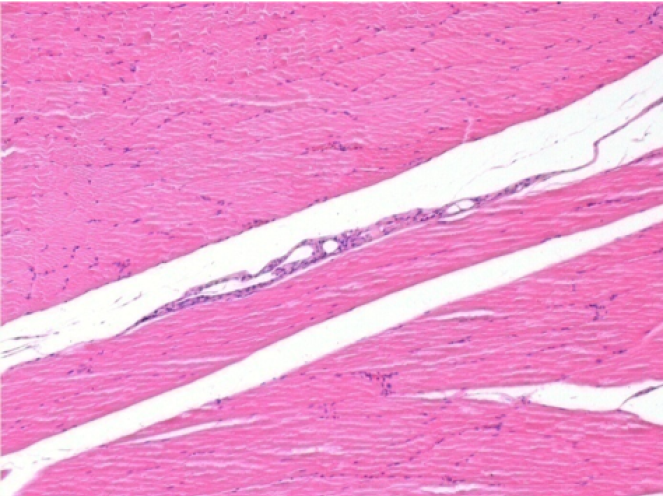

سبعة أشهر بعد حقن إندوبيل

7 أشهر (D210) بعد حقن Endopeel IM 0.1 مل في العضلة أمام الظنبوب اليمنى.

Complete Restitutio ad integrum after 7 months

L : Control-100xD210

R:100xD210

L :Control 50xD210

R50X-D210

يستحث Endopeel انحلال عضلي عضلي قابل للانعكاس الانتقائي ورد فعل التهابي في فترة شهر واحد تقريبًا

- التغييرات العضلية قابلة للانعكاس في مجملها بالكامل تقريبًا

- العضلة هي أفضل مكان لحقن Endopeel بسبب فعاليتها وتحكمها ومدة عملها

- لم يتم العثور على أي نخر أو خراج في جميع أنحاء الدراسة.